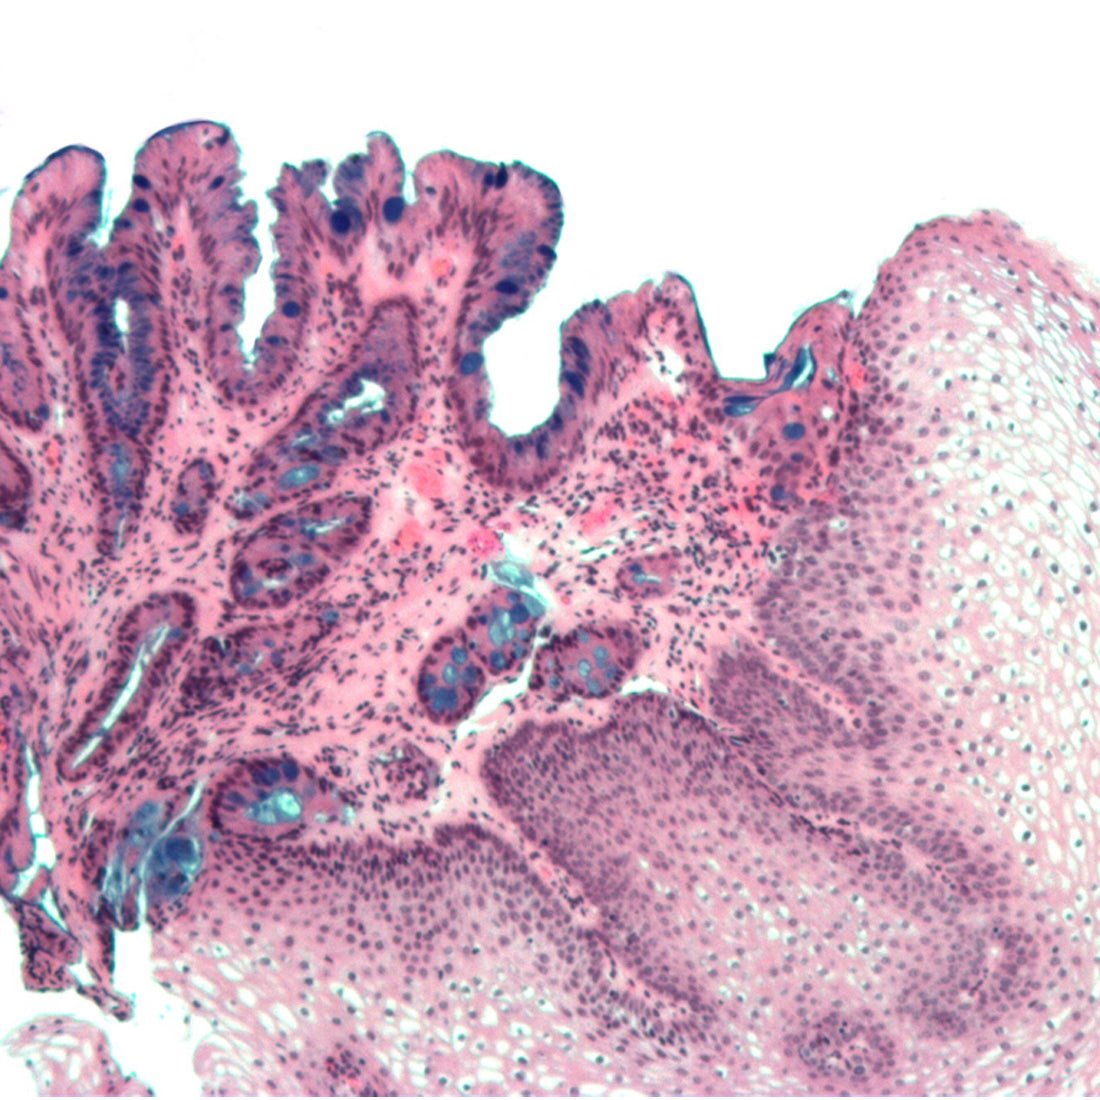

This is a combined method utilizing the properties of both PAS and Alcian blue pH 2.5 methods to demonstrate the full complement of tissue proteoglycans. Alcian Blue pH 2.5 stains the acid mucins blue while PAS stains the neutral mucins pink to red.

- Acid mucins- blue

- Neutral mucins and other PAS positive tissue elements- pink to red

- Acid and neutral mucins mixtures- purple